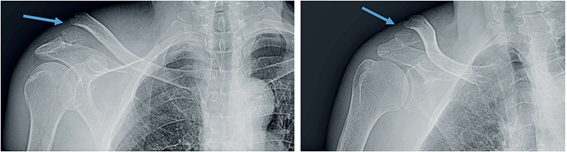

Paciente masculino de 76 años, dominancia derecha, quien ingresó a urgencias por caída desde su propia altura. Al examen físico presentaba deformidad en la clavícula derecha y las radiografías mostraron fractura desplazada del tercio distal de la clavícula (Figura 1), por lo que fue llevado a cirugía para reducción abierta, fijación interna con placa anatómica bloqueada de clavícula y fijación con dos clavos de Kirschner. La radiografía postquirúrgica mostró material de osteosíntesis con adecuada reducción de la fractura (Figura 2). El paciente evolucionó satisfactoriamente, se dió de alta con analgésicos orales y citó a control por consulta externa.